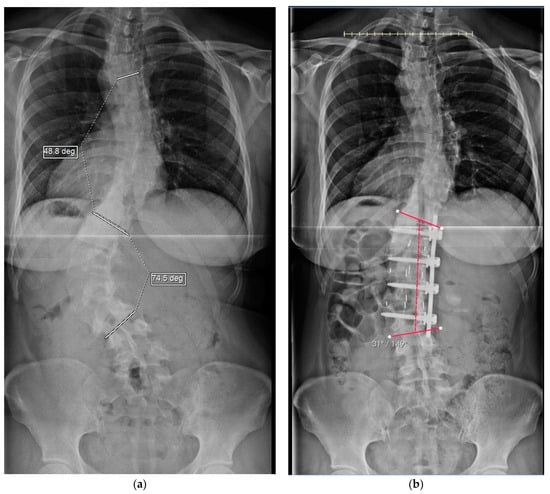

3.2. Radiographic Findings

Preoperative radiographic findings (Table 1) found similar mean preoperative scoliotic curves of the lumbar (thoracolumbar) regions measuring 53° for both the concave and for the traditional convex groups (Table 1; the significance column represents the p-value between the two cohorts). Postoperative curves were a mean of 18° and 19° for the concave and convex groups, respectively, which was predicted by their preoperative bending radiographs. The mean change in both groups was 34° (65% improvement). Compensatory thoracic and lumbosacral curves improved uniformly. The coronal radiographic improvements (TL/L primary, and compensatory T and LS scoliosis) were all significant for both groups (p < 0.02). It is also notable that the median number of levels fused in the concave group was three, whereas in the convex group it was four. Additionally, the LIV was lower, on average by ½ level, for the traditional cohort. Preoperative coronal imbalance was similar in both groups. Postoperatively, the coronal decompensation was reduced to 0.5 cm and 1.2 cm in the concave and convex groups, respectively. Sagittal parameters remained stable. Between the two cohorts, there was no significant difference in these preoperative and postoperative radiographic parameters. Four patients had notable distal junctional disc degeneration of which two were fused to below L3, and one had a residual deformity of the lumbosacral curve of 17°.